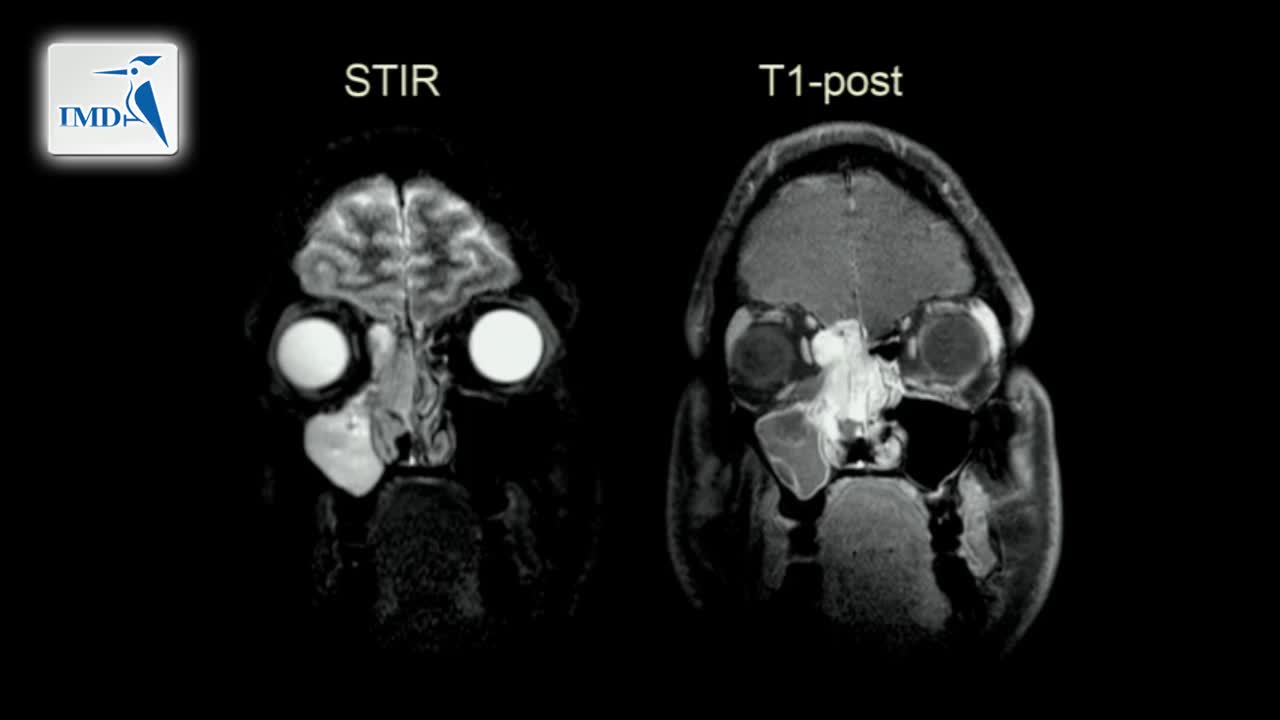

《神经科》2019年第4讲(总第159讲)基于病例学习神经影像学(4)

《神经科》2019年第2讲(总第157讲)基于病例学习神经影像学(2)

《神经科》2019年第1讲(总第156讲)基于病例学习神经影像学(1)